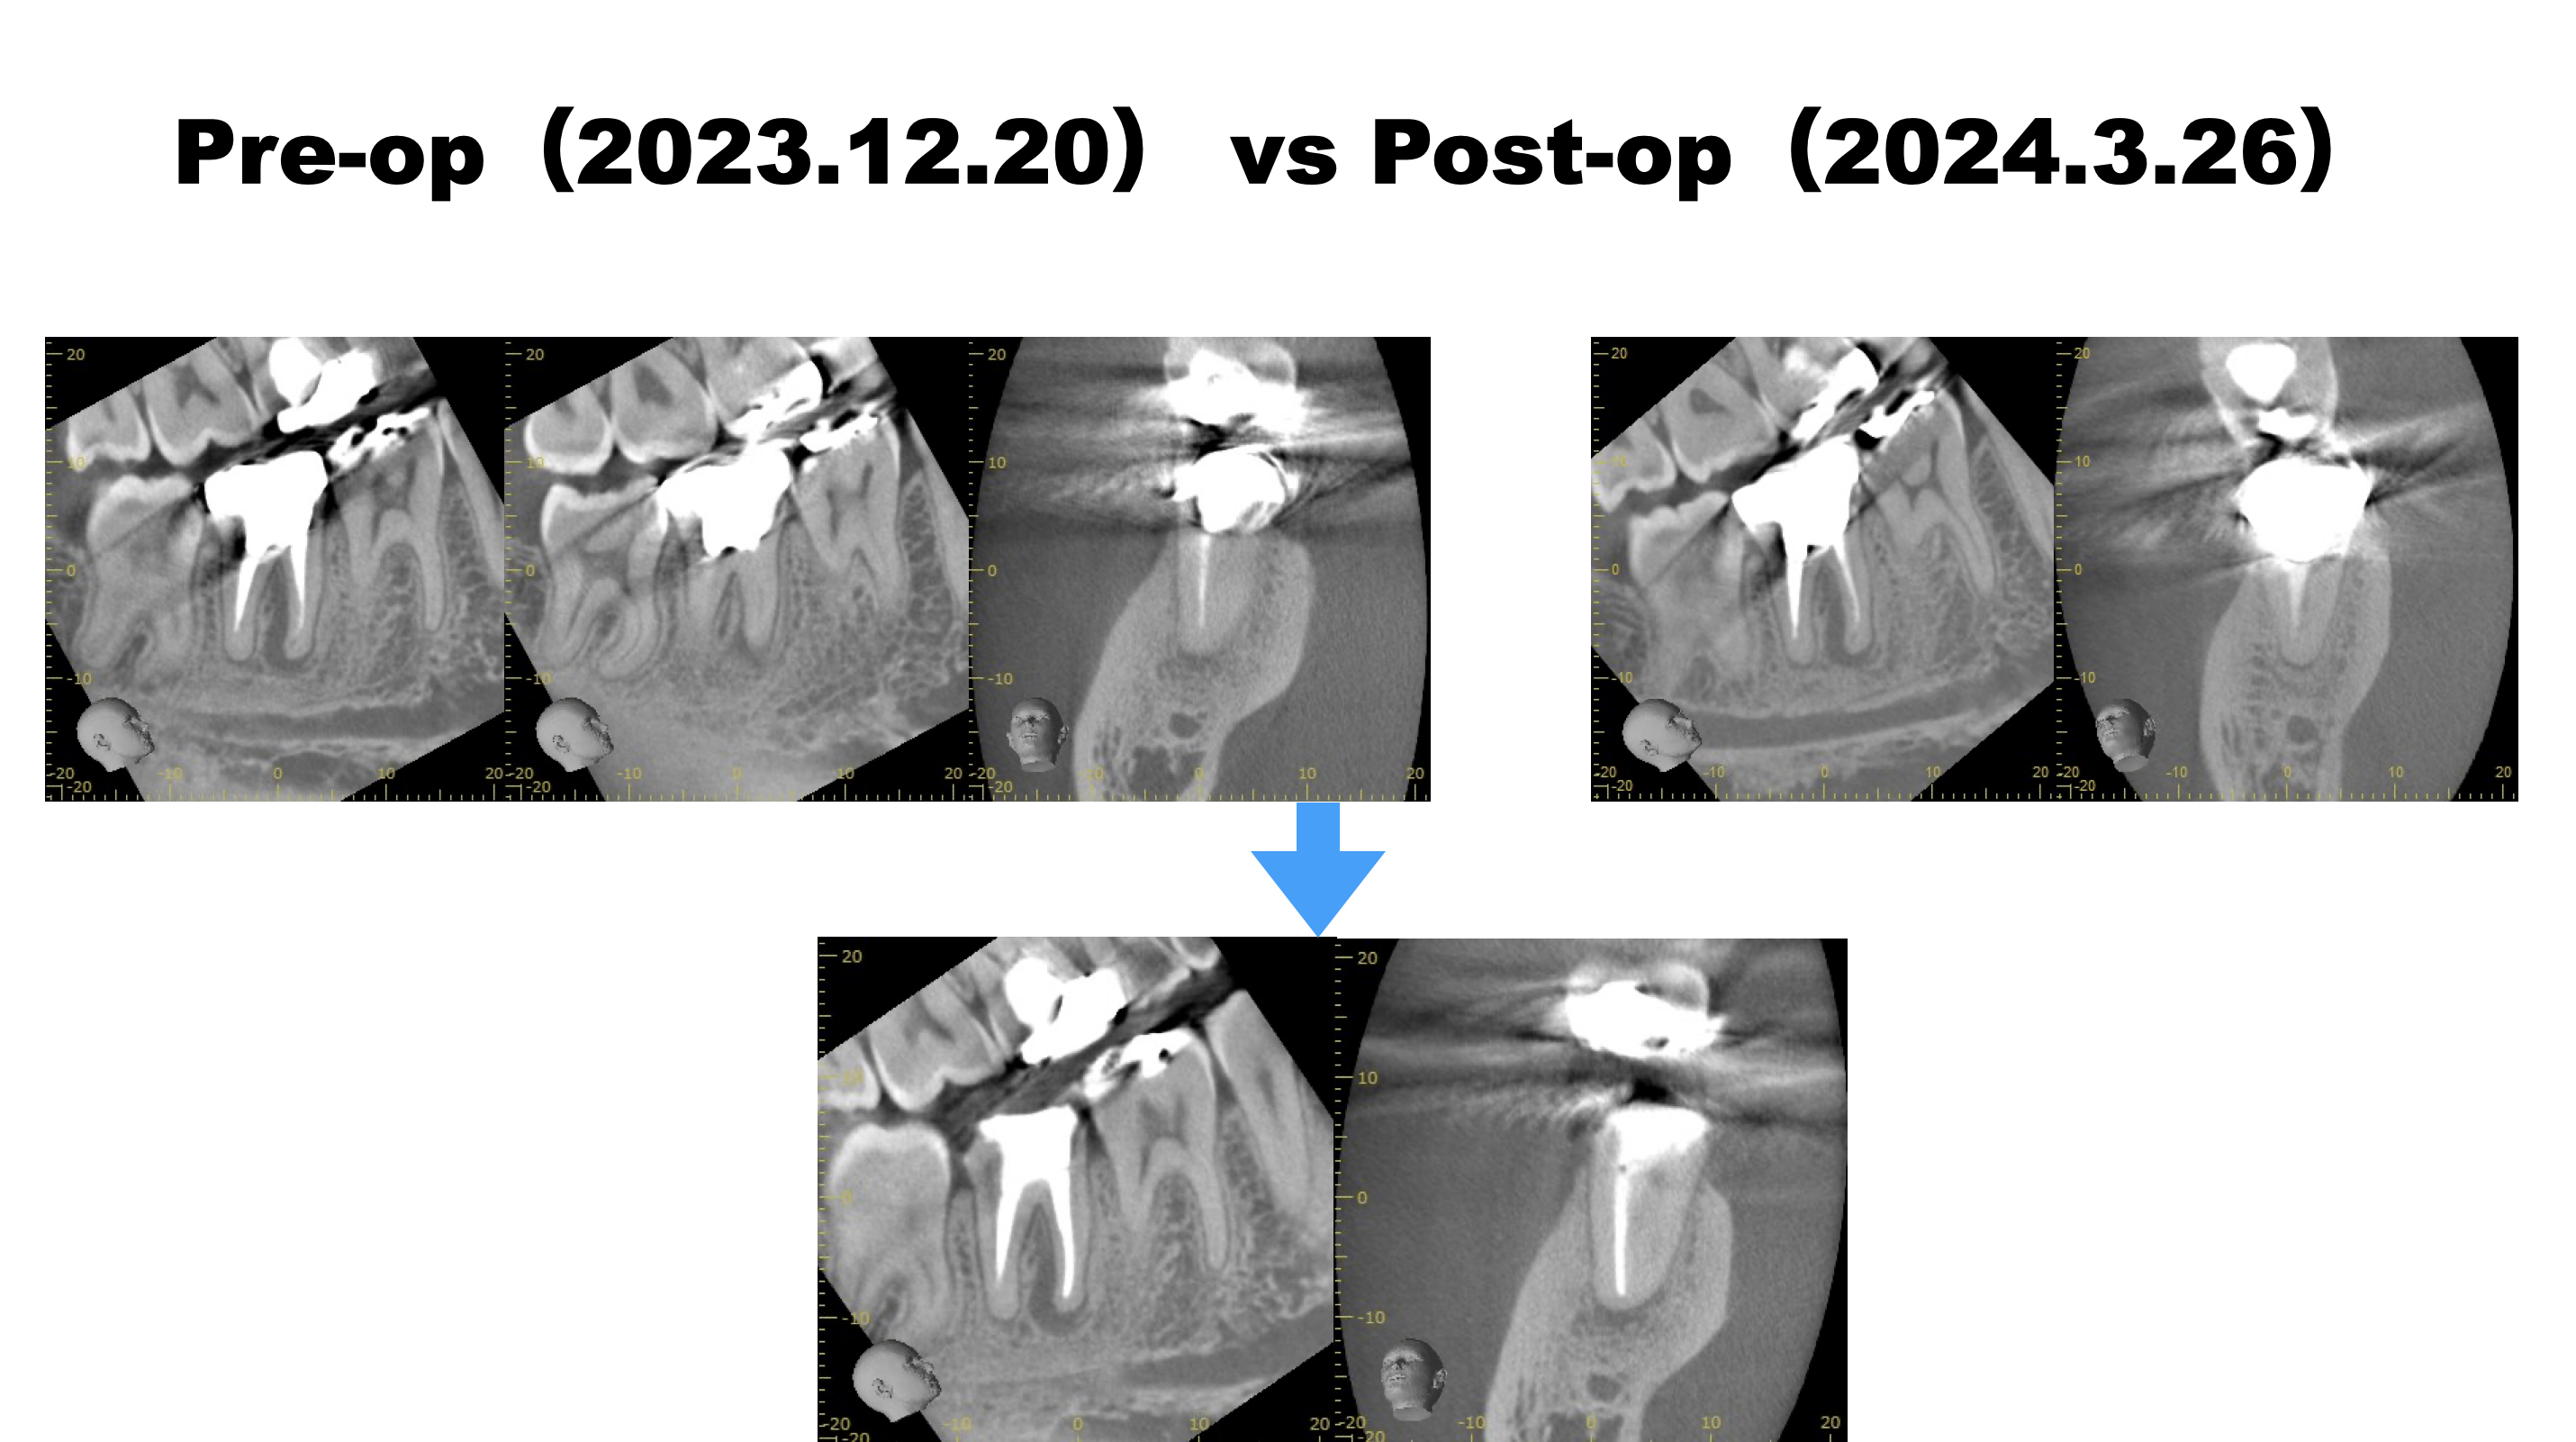

#30 Re-RCT(2024.3.26)

MLは石灰化が亢進している。

穿通するだろうか?というよりも、ProTaper SXでコロナルフレア形成できるだろうか?

ともかく、SXを使用するにはそれが入る道を作らねばらない。

短針で、スカウティングした。

その後、SXを使用したが

SXでコロナルフレア形成はできなかった。

そのような時、どうするべきだろうか?

といえば、

どうもできないのである。

つまりこの時点で、

MLは形成が不可能である

という事実がわかる。

MBのみの根管再形成に着手して根充した。

術後にPA, CBCTを撮影した。

MLは石灰化が亢進しており何もできなかった。

これで治癒するか?は神様が決めることである。

ということで次回は半年後である。

またその後の経過をお知らせしたい。